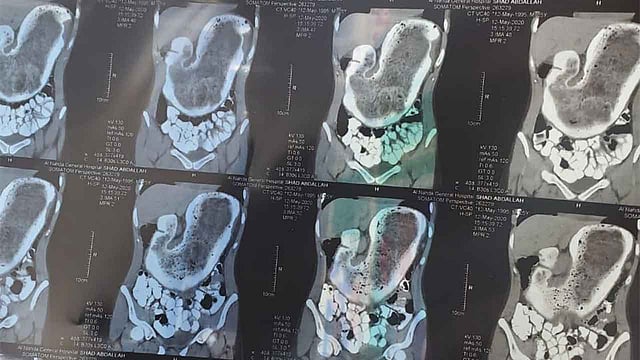

أخرج فريق طبي بالطائف، 2 كيلو من الشَعر داخل بطن فتاة عشرينية، بعدما لازمتها آلام مزمنة.

وكانت الفتاة قد قادتها أوجاعها المتكررة لطوارئ مستشفى الملك عبدالعزيز التخصصي بالطائف، بعد أن أعياها الألم ووصلت معه إلى حد لا تستطيع مقاومته، لتخضع لفحص سريري موسع، انتهى بالوصول لعلة الفتاه منذ سنوات، بعد اكتشاف جسم غريب يتمحور داخل البطن ويشكل جدارًا خانقًا للمعدة.

وعلى الفور قرر الفريق الطبي بقيادة استشاري الجراحة بالمستشفى التخصصي الطبيب محمد المهدي، وزميلاه أخصائي الجراحة محمد عبده، والطبيب محمد الزهراني، وطاقمهم الفني، إجراء تدخل عاجل للوصول للجسم الغريب ليكتشفوا لاحقاً أن ما كان يحيط بالمعدة وكان سبب آلام سنوات مضت، عبارة عن تشكل مترابط من الشعر يزن 2 كيلو جرام، استطاعا التكتل حول جدار المعدة داخل تجويف البطن مع تزايد نموه في حالة طبية نادرة الحدوث.

وتم استخراج الكتلة وإنهاء معاناة الفتاة بإذن الله لتنعم بالراحة، وهي في صحة جيدة برعاية سريرية من الطاقم الطبي بالمستشفى حيث ما زالت هناك.